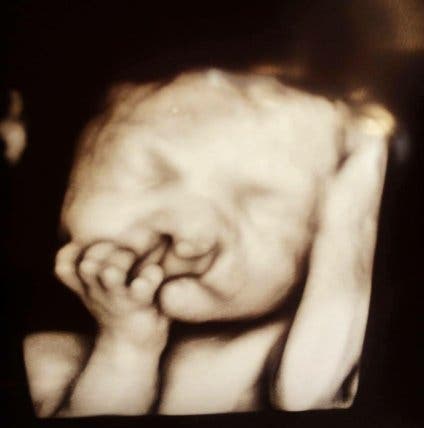

A l’annonce de la nouvelle bouleversante, les jeunes parents ne cachent pas leur choc. Les résultats de l’échographie montrent clairement la malformation de leur bébé, une situation difficile à laquelle le couple n’était vraisemblablement pas préparé. Face aux alternatives proposées par les médecins, leur réponse apparaît comme une évidence : il n’est pas question de faire un choix.

Selon des données recueillies dans six régions de l’Hexagone et des Outre-mer, Santé Publique France estime que le nombre de nouveau-nés et de fœtus porteurs de maladies congénitales avoisinerait les 28 000 cas par an, soit 3,4 cas pour 100 naissances. Des chiffres approximatifs selon l’agence mais qui reflètent une réalité à laquelle de nombreux parents sont confrontés avant et/ou après la naissance et ce, à travers le monde entier. Pour Sara et Chris, jeune couple américain, leur vie sera transformée après 24 semaines de grossesse. Selon le diagnostic des médecins, leur enfant sera porteur de fentes labio-palatines. Une malformation qui toucherait un enfant sur 750 en France.